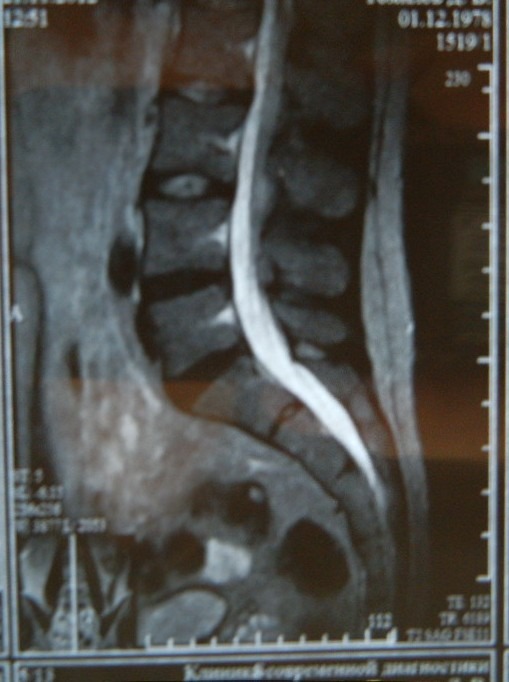

| А тут задран крестец или нет? Вроде да, а то у меня с определением траблик...

по моему таз вперед упал

Что бы сказать определенно, что произошло одного МРТ не достаточно, мог таз "упасть", а мог и крестец "задраться", а может и одновременно.

Пока только видно, что есть гиперлордоз- а вот причина...

Хмммммм.... по данным мрт - физиологический поясничный лордоз выпрямлен ...а гиперлордрз это же вроде как нооборот сильнее изгиб и пузо вперёд